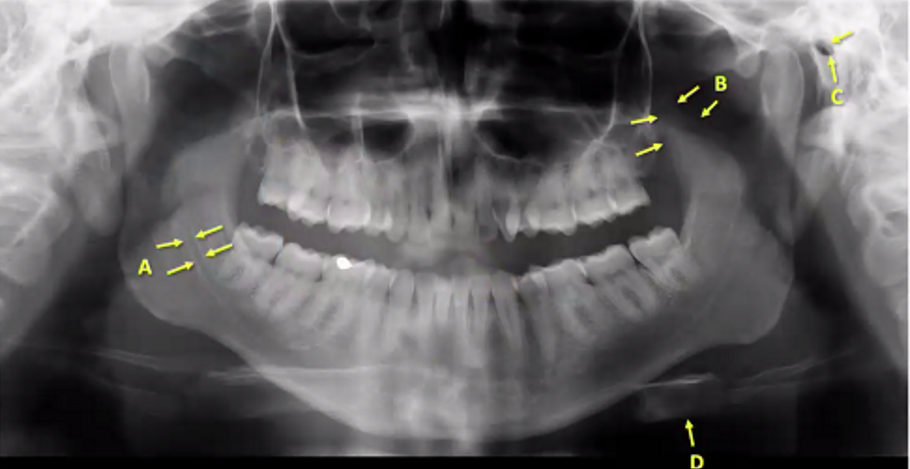

types of radiograph

maxillary anterior occlusal and mandibular occlusal

A

nasal septum/vomer (white so bony)

B

medial wall of maxillary sinus

C

medial or midline palatal suture

D

genial tubercle